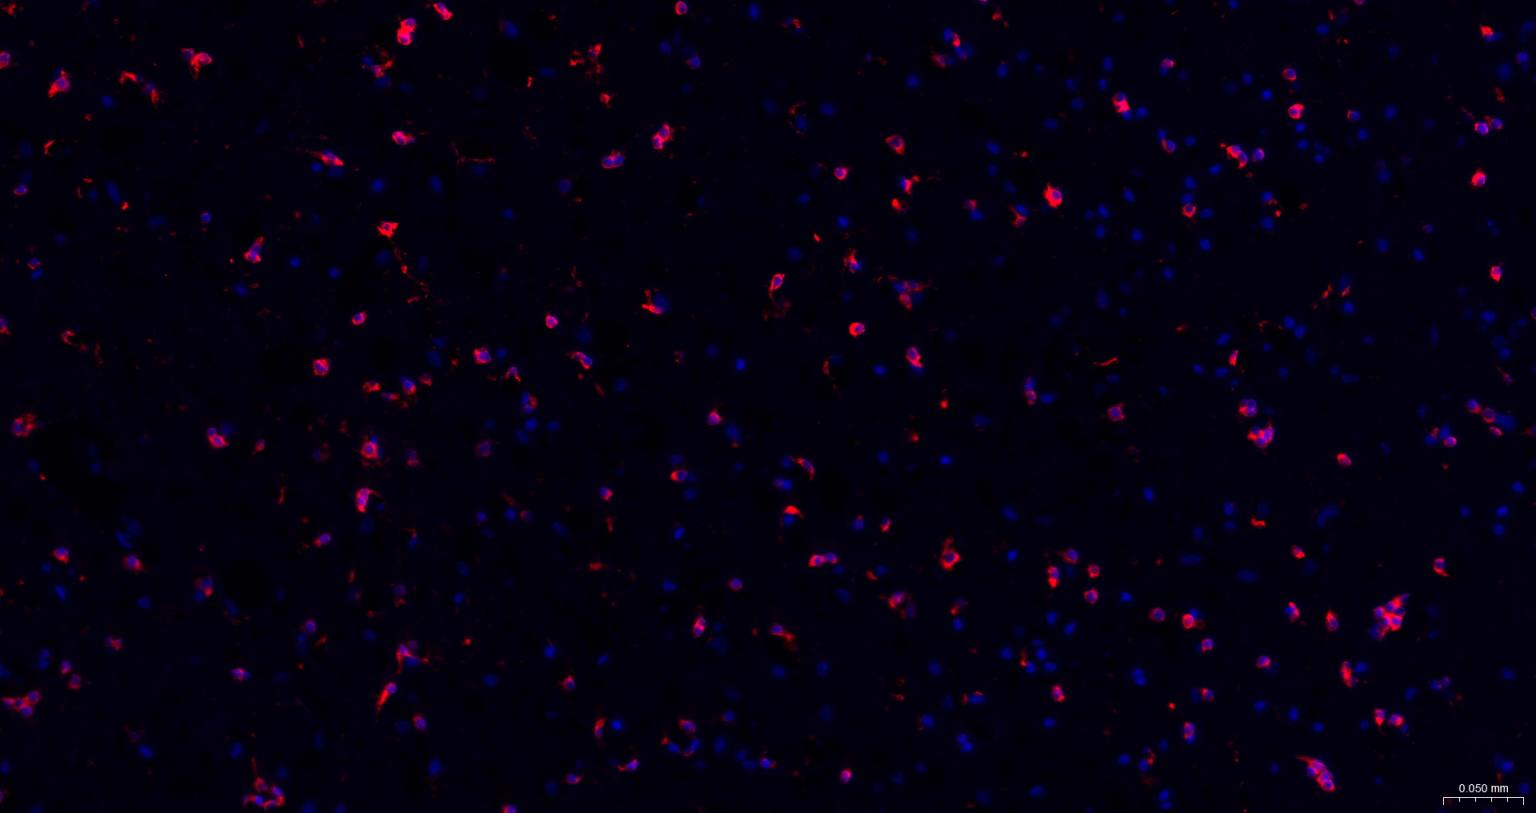

神经细胞标志物

(NMDAR1)N-甲基-D-天门冬氨酸受体(NMDAR)是兴奋性氨基酸受体亚型之一,是由NMDAR1与不同的NMDAR2亚基组成的异聚体。

The protein encoded by this gene is a critical subunit of N-methyl-D-aspartate receptors, members of the glutamate receptor channel superfamily which are heteromeric protein complexes with multiple subunits arranged to form a ligand-gated ion channel. These subunits play a key role in the plasticity of synapses, which is believed to underlie memory and learning. Cell-specific factors are thought to control expression of different isoforms, possibly contributing to the functional diversity of the subunits. Alternatively spliced transcript variants have been described. [provided by RefSeq, Jul 2008]

| IF | Human, Mouse, Rat | 1:100-500 |